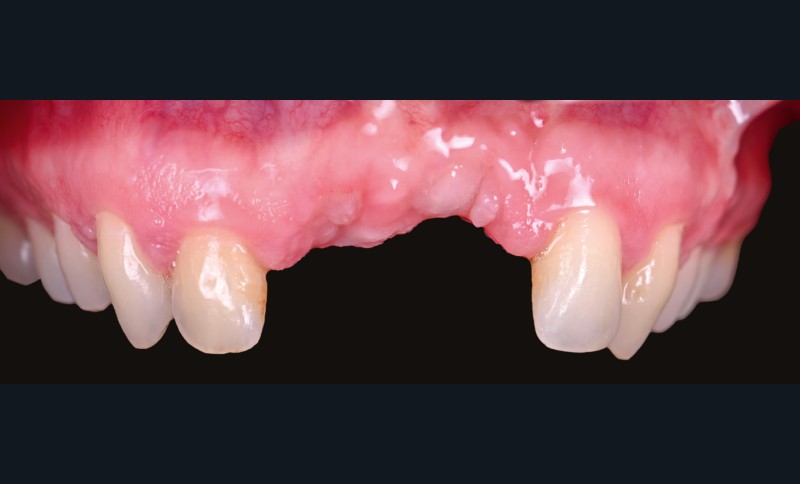

La chirurgie implantaire nécessite fréquemment des procédures de greffe osseuse pour pallier les déficits volumétriques et permettre un positionnement idéal des implants. Le défaut osseux peut être lié à de nombreux facteurs : extraction ancienne, prothèse amovible, séquelles iatrogènes. La technique de Split Bone Bloc (ou technique Shell), développée par F. Khoury, est une méthode efficace mais réservée à des praticiens expérimentés, en raison de sa technicité et de la morbidité associée à un prélèvement rétromolaire mandibulaire.

L’avènement des technologies numériques a permis d’améliorer la précision de ces procédures. La planification implantaire 3D, associée à la conception et fabrication assistée par ordinateur (CAD/CAM), permet aujourd’hui de concevoir des guides chirurgicaux spécifiques optimisant et sécurisant le positionnement des blocs osseux. De même, la démocratisation récente des techniques de chirurgie guidée dynamiques par caméra stéréoscopique constitue un outil attractif pour les techniques de reconstruction osseuse. Ainsi, la taille du bloc à prélever sur la zone rétromolaire mandibulaire peut aussi être exactement déterminée en amont de la chirurgie (fig. 1 et 2).